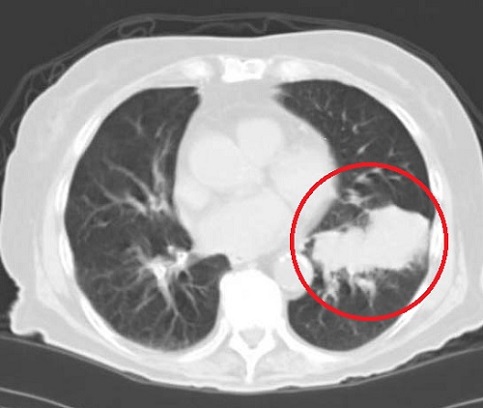

Березень 2009 Грудень 2009

Комп’ютерна томографія: зменшення пухлини у пацієнтки з недрібноклітинним раком легені.

Пацієнтка не приймала хіміотерапію і регулярно пила канадський чай «Ессіак».[5]

Дослідники з Університету Торонто (Онтаріо, Канада) і клініки радіологічної онкології Лікарні Принцеси Маргарет (Онтаріо, Канада) д-р Gladwish і д-р Clarke описали випадок зменшення пухлини легені і скорочення пухлинного ураження лімфовузлів середостіння у пацієнтки, яка не отримувала хіміотерапію, а регулярно приймала тільки чай «Ессіак». Звіт про цей унікальний випадок був опублікований в 2010 році у British Medical Journal [5]